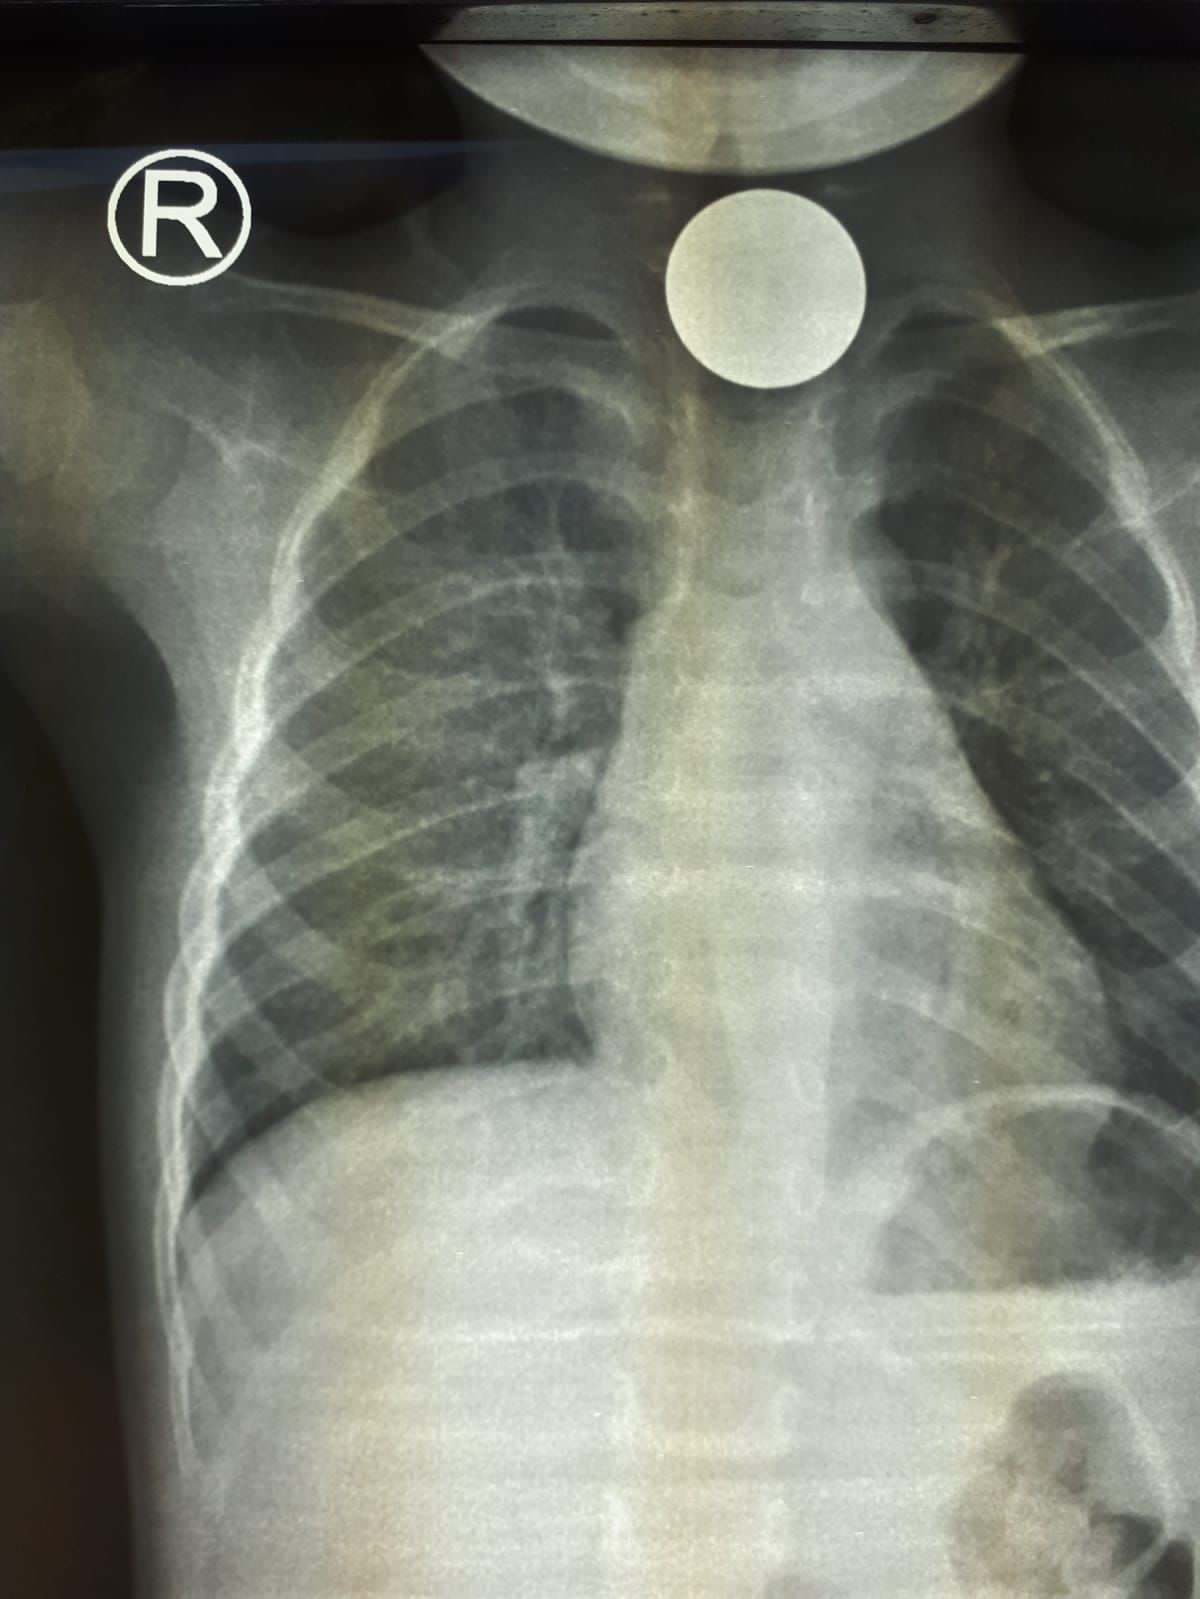

تمكن - بفضل الله - فريق طبي بمستشفى رابغ العام من استخراج قطعة معدنية من بلعوم طفل يبلغ من العمر عامان خلال عملية لم تستغرق أكثر من 10 دقائق.

وأوضحت (صحة جدة) أن الطفل قَدِم إلى طوارئ المستشفى وهو يشكو ابتلاع جسم غريب (قطعة نقود معدنية) كانت قد علقت في منطقة البلعوم؛ مما تسبب في اختناق وعدم قدرة على البلع؛ حيث قرر الطاقم الطبي إجراء عملية عاجلة بالمنظار لإزالة الجسم الغريب، والتي تبين أنها قطعة معدنية نقدية، وقد كُللت العملية بالنجاح  دون حدوث مضاعفات - ولله الحمد - وقد غادر الطفل المستشفى وهو بصحة جيدة.